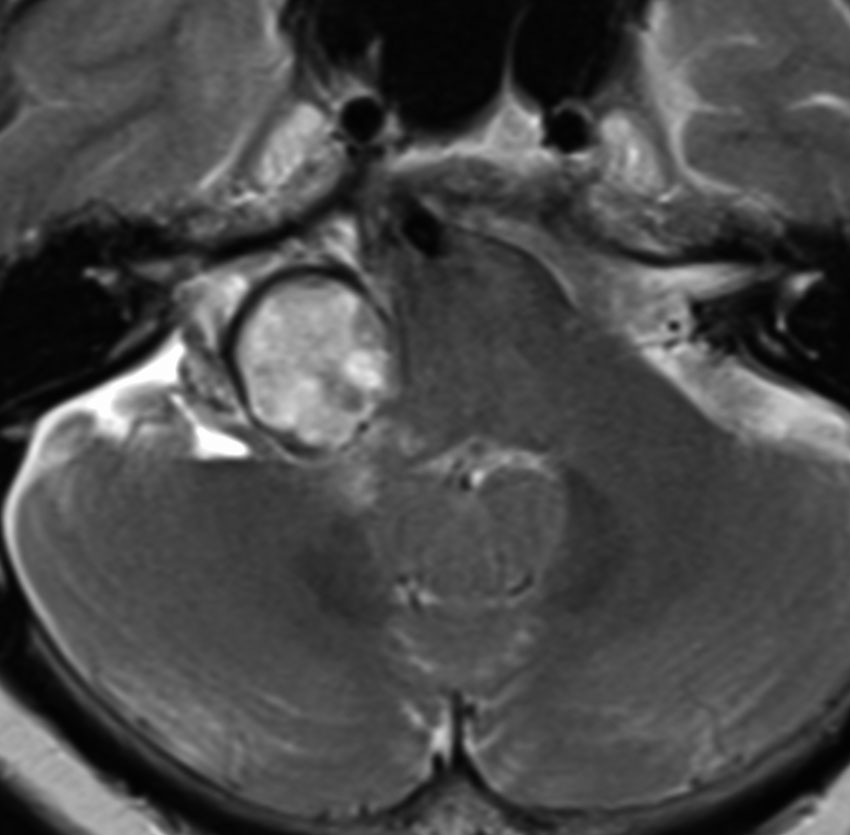

この腫瘍は脳幹部変形がとても強く,大きいので手術摘出するしか選択肢はありません

- 脳幹部の変形が高度な大きな腫瘍になると手術するしかありません

- 4cmを超えると危険だと考えてください

- 巨大な充実性の聴神経腫瘍の手術では命をなくすリスクもあるものです

聴神経腫瘍でまず手術が必要なのは巨大なものです。この4枚の写真は私が実際に手術をした患者さんのものです。脳幹部という脳の最も大切なところが腫瘍によって圧迫されて変形しているのが特徴です。右上のものはのう胞性腫瘍なので大きさの割に手術のリスクは高くありませんが,左上のものは実質性で出血性のものですごくリスクが高い手術でした。左下のものは普通のリスク。右下のものは超高難易度のものです。